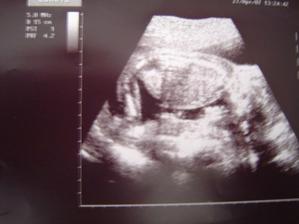

Nas pokladik Adamko

Asi presne na Vianoce 2006 sa nam podarilo stvorit maly zazrak, ktory bude snad pekne rast a robit nam radost 🙂

11.9. 2007 sa nam pokladik narodil a vola sa Adamko.